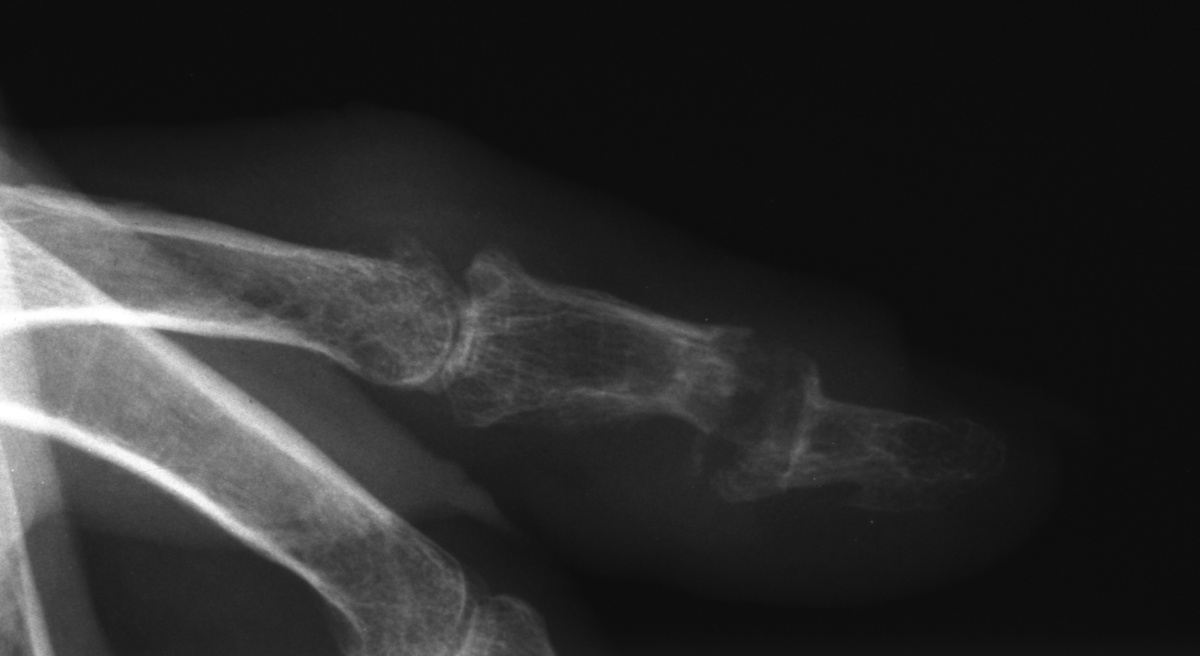

| Left index distal

interphalangeal joint tophus with thin overlying skin and nail

deformity. |

| Despite extensive

remodelling, the joint had 50 degrees of active motion. |